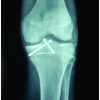

A 20-year-old young male presented to the emergency department following road traffic accident and on probing the patient, he had fallen with a flexed knee leading to axial impaction of tibial condyle over the posterior femoral condyle. Patient had an open lacerated transverse wound about 7 cm over the anterior aspect of the knee. The distal end of femur was protruding out along the avulsion of patellar tendon from the insertion site. Clinical examination was not possible because of open wound and intense pain. There was no distal neurovascular deficit and patient was hemodynamically stable. Radiological examination of the involved knee included the anterior-posterior and oblique views (Fig. 1) showing patella alta, suggesting the patellar tendon avulsion with fracture of anterior tibial spine and lateral-oblique view showing non-conjoint bicondylar Hoffa fracture.

Initially, wound was debrided and an external fixator applied. The second procedure was taken after 2 days and both femoral condyles approached through the same open wound. The bicondylar Hoffa fracture was fixed with two 6.5 mm partially threaded cannulated cancellous screw. Screws were inserted from the non-articular portion of the femoral condyle on knee flexion. The anterior tibial spine fragment was fixed with 4.0 mm partially threaded cannulated cancellous screw and the patellar tendon avulsion was fixed to the tibia with ethibond trans-osseous suturing (Fig. 2). The wound was primarily closed without the need of additional soft-tissue procedures. The patient was kept in external fixator for 6 weeks in view of healing of the patellar tendon and soft tissue.